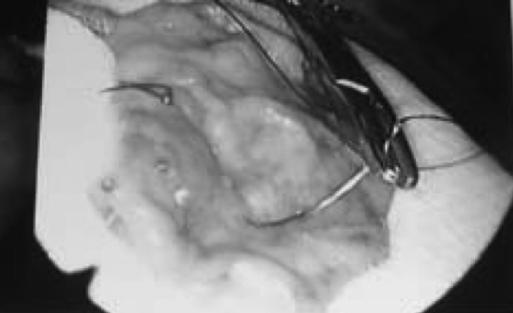

A 70-year-old female with a history of bleeding from Osler-Weber-Rendu disease presented to the emergency department complaining of hematemesis. Her vital signs were unstable, and she was immediately resuscitated with intravenous fluids and transfusions. A combined laparoscopic and intraoperative endoscopic approach to a partial gastric resection was planned. Intraoperatively, a single lesion was identified along the posterior aspect of the greater curvature of the stomach by using endoscopy. The blood supply was taken down with a Ligasure and gastric resection with a 60-mm Echelon stapler.

一名有遗传性出血性毛细血管扩张症出血史的70岁女性因呕血就诊于急诊科。她的生命体征不稳定,立即通过静脉输液和输血进行复苏。计划采用腹腔镜和术中内镜联合进行部分胃切除术。术中,通过内镜在胃大弯后侧发现一个单一病变。使用结扎速血管闭合系统切断血供,并用60毫米的Echelon吻合器进行胃切除。